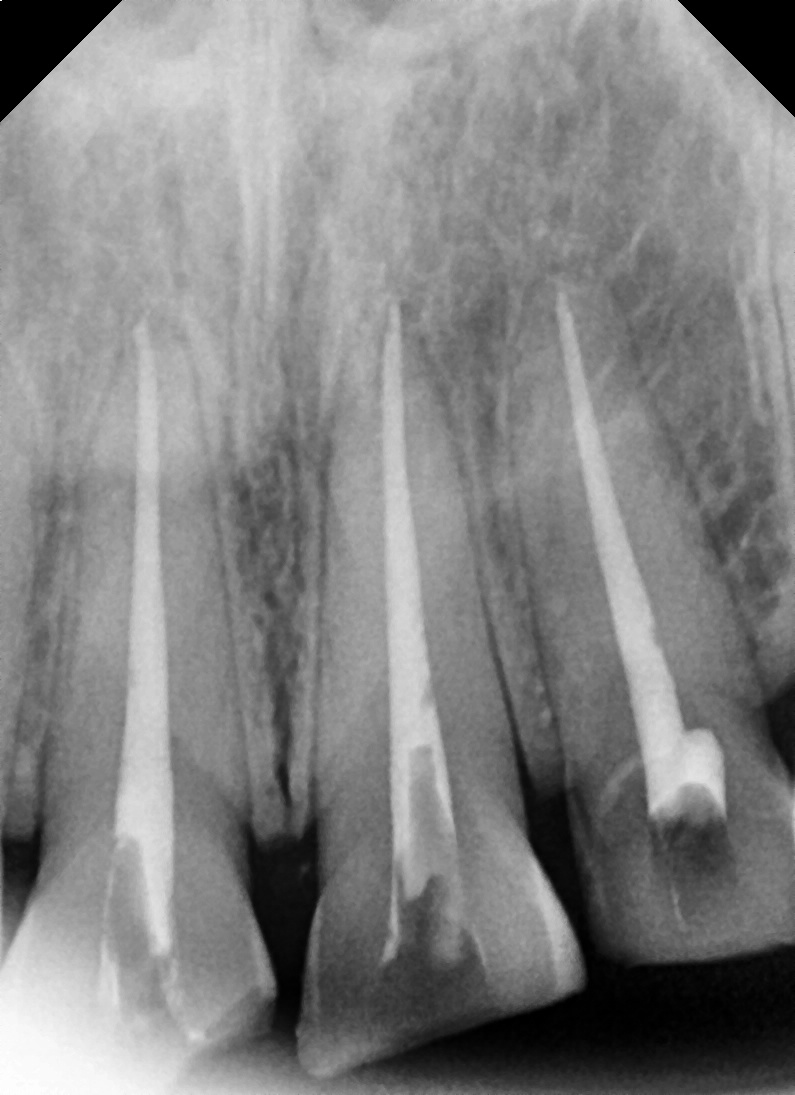

① Root canal treatment

– Removed inflammation and damaged pulp inside the tooth,

and prevented infection through root canal therapy.

② Tooth shaping

– After shaping the tooth so the crown would fit properly,

we placed a temporary restoration.

③ Final crown fabrication

– A zirconia crown was custom-made in the hospital’s in-house lab.

– We reflected the bright, natural color desired by the patient.